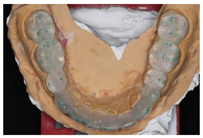

制作上颌活动

垫:调磨过锐牙尖,取印模,正中关系位记录

关系,制作上颌活动

垫,调磨使后牙功能尖均匀接触,侧方

无干扰。此病例

垫做在上颌,因其下前牙牙冠短,不至于引起前伸

干扰,引起关节后移(图14,图15)。戴用

垫三月后:双侧颞下颌关节及肌肉未诉不适,肌肉触诊上颌结节疼痛减轻,翼内肌疼痛消失。CBCT示:戴用

垫时咬合位拍摄,双侧髁突位置居中,骨质未见确切异常改变(图16)。